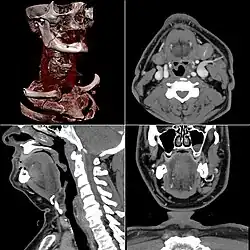

Celles-ci se présentent sous la forme de « coupes » ou tranches d'épaisseur millimétrique (de 0,4 mm à 10 mm) que le radiologue peut étudier dans tous les plans de l'espace (sagittal, axial, coronal et obliques), et qu'il s'agit de post-traiter (augmentation de l'épaisseur des coupes visualisées, mise en valeur de certaines densités, reconstructions volumiques en 3D, extraction des vaisseaux ou des structures osseuses, navigation virtuelle endoscopique, etc.).

Images obtenues après traitement des données.